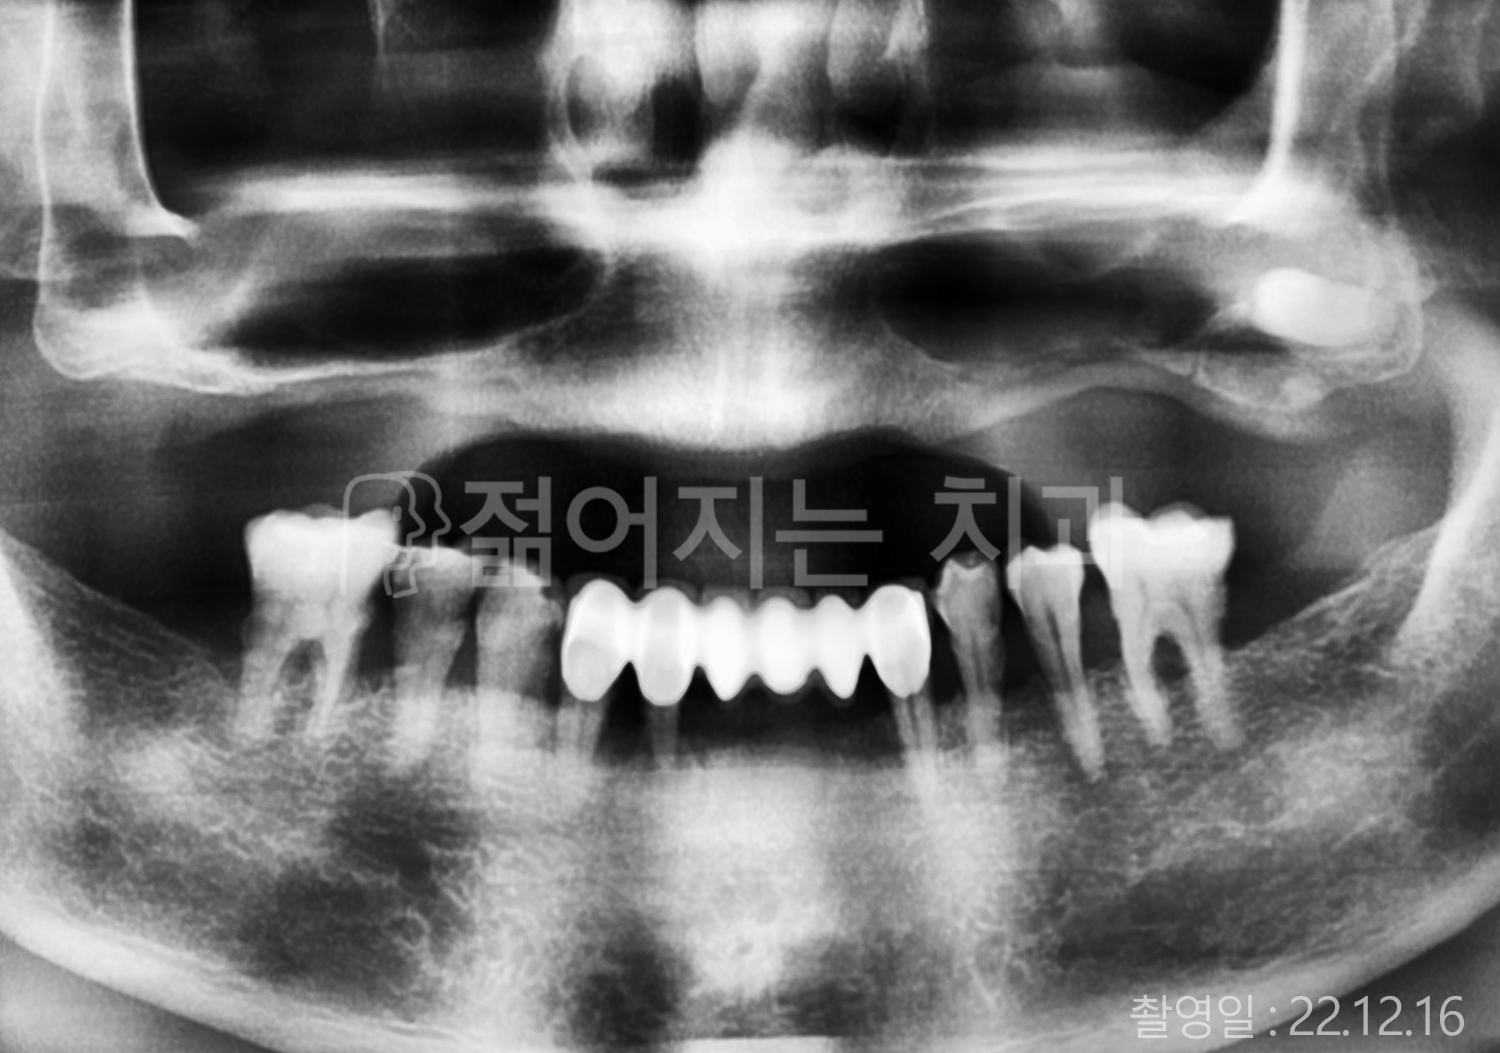

• 40대 전체치아 10개 이상 임플란트

• 70대 당뇨 전체치아 10개 이상 임플란트

• 60대 전체치아 10개 이상 임플란트

• 60대 고혈압, 당뇨, 고지혈증 전체치아 10개 이상 임플란트

• 50대 전체치아 10개 이상 임플란트

• 70대 고혈압, 당뇨 전체치아 10개 이상 임플란트

• 60대 고혈압 전체치아 10개 이상 임플란트

• 50대 고혈압, 당뇨, 고지혈증 전체치아 10개 이상 임플란트

• 60대 고혈압, 고지혈증 전체치아 10개 이상 임플란트